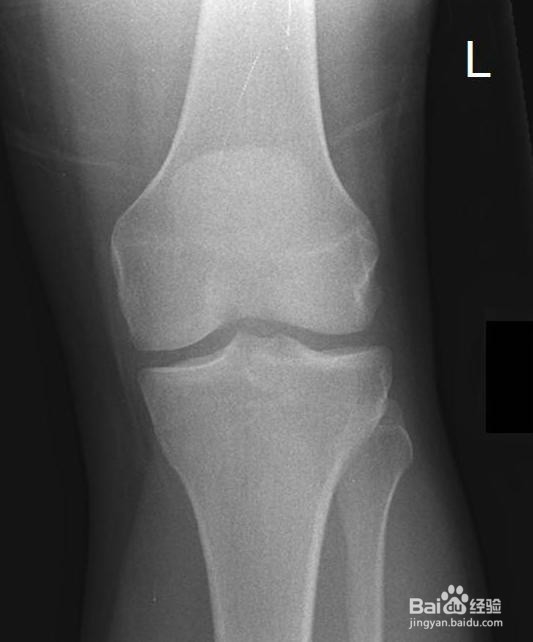

2、X光透视检查。通过X光拍摄关节部位的透视图片,可以直观的看出关节是否存在结构上的病变,从而判断是否有骨折的现象。